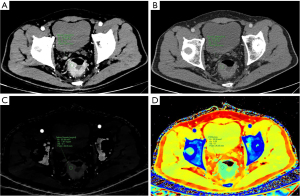

Table 3 and Figure 2 show the results of the SDCT quantitative parameter analysis for the two groups. CT40keV [175.14 (152.90, 194.94) vs. 152.65 (119.29, 176.93) HU, P=0.02], CT120keV (49.19±6.14 vs. 44.19±7.36 HU, P=0.007), IC [1.68 (1.35, 1.84) vs. 1.36 (1.00, 1.64) mg/mL, P=0.02], NIC [0.15 (0.12, 0.18) vs. 0.11 (0.09, 0.14), P=0.002], Zeff [8.23 (8.08, 8.31) vs. 8.09 (7.90, 8.24), P=0.048], NZeff [0.73 (0.71, 0.75) vs. 0.70 (0.68, 0.74), P=0.008], λHU [1.64 (1.32, 1.76) vs. 1.32 (0.98, 1.60), P=0.03] in the arterial phase and AEF [0.74 (0.63, 0.85) vs. 0.60 (0.49, 0.76), P=0.01] were higher in the low-grade TB group than in the high-grade TB group. No significant difference was observed in the spectral characteristics of the venous phase between the two groups (P>0.05). Figures 3,4 show spectral CT multiparametric images of high-grade and low-grade TB in CRC, respectively.

Microvessel density (MVD), a measure of tumor angiogenesis, is associated with tumor blood supply. Higher MVD values signify more angiogenesis and a more substantial blood supply (37). In our study, the spectral characteristics of the low-grade tuberculosis group were elevated compared to those of the high-grade tuberculosis group, indicating that the former exhibited a more abundant blood supply and increased microvascular density. This conclusion corresponds with the work of Righi et al. (38), which indicated markedly elevated MVD in the low-grade tuberculosis group relative to the high-grade group in CRC. In addition, Righi et al. also showed that TB correlated with hypoxia resulting from inadequate blood supply at the tumor’s advancing front, and the expression of hypoxia-inducible factor-1a (HIF-1a) was higher in high-grade TB CRC. Hypoxia may stimulate tumor angiogenesis and lymphangiogenesis. However, the resultant neovascularization is often architecturally deficient and functionally aberrant. This may result in hypoxic circumstances and increased interstitial pressure inside the tumor (39), possibly leading to diminished blood perfusion and explaining the lower spectral values seen in the high-grade TB group.

To reduce the effects of individual variability, vascular variables, and contrast agent volume, we used IC and Zeff of the aorta at the same ROI level as reference points for computing NIC and NZeff. Standardization enhanced the AUC and specificity of NIC and NZeff. Shao et al. (23) showed an inverse connection between NIC and tumor TB grade, aligning with our results. Moreover, our findings indicated that NIC in the arterial phase had the highest AUC (0.723) for differentiating between high and low-grade TB in CRC among individual parameters. Further study indicated that the diagnostic efficacy of integrated spectral characteristics from the arterial phase and AEF surpassed that of any single parameter, with an AUC of 0.814, a sensitivity of 84.62%, and a specificity of 72.73%.